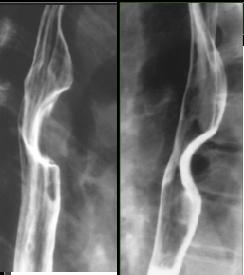

5 Leiomyome

: Le plus frequence des tumeurs begnines et le plus

souvent 2/3 inferieure de oesophage . Image TOGD baryte

et TDM est une masse unique , homogene polylobee et

pseudocapsule avec contour bien limite . Signe clinique

est : douleur thoracique , et dysphagie

Image TOGD de leiomyoma du

portion inferieure de oesophage . Image laculaire

intramurale: bord net , lisse a inferieure de

oesophge |

Image TOGD en double de contrast : Tumeur

intramurale bord lisse reduisent l /2 lumiere

de oesophage |